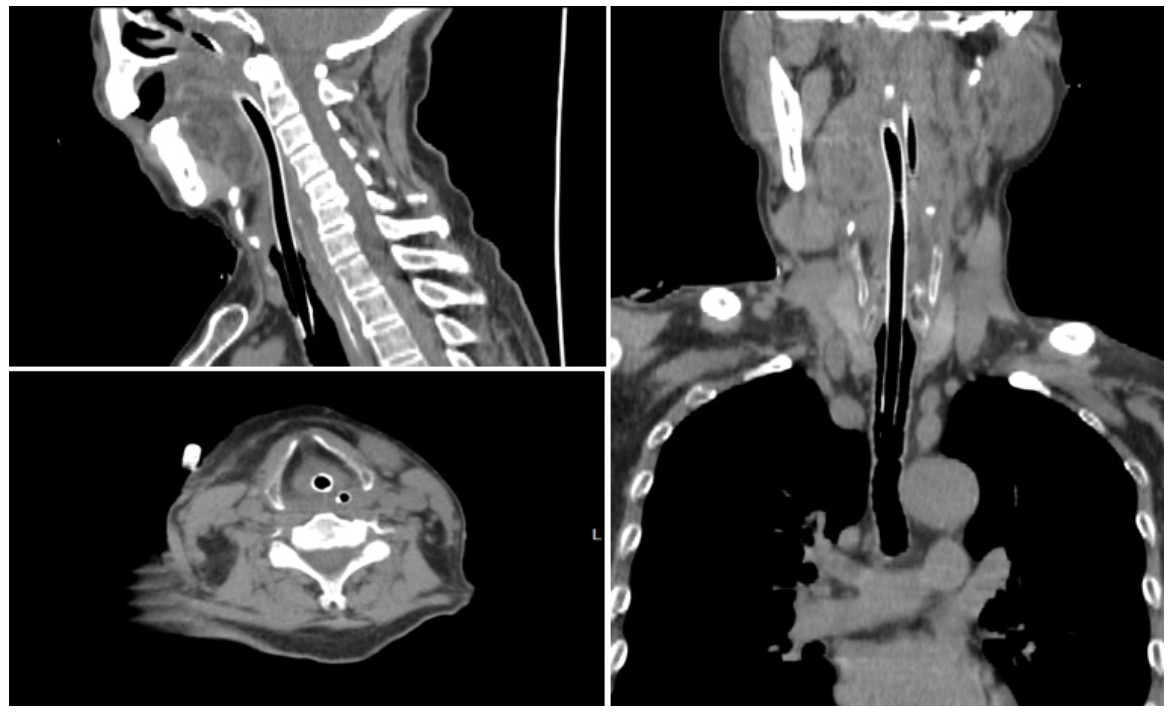

急诊观察室留观约5 min患者突然出现高度吸气性呼吸困难,三凹征明显,口唇发绀,烦躁不安,起身用手抠抓颈部,心电监测显示SpO2快速进行性下降,最低达20%左右,心率亦伴随SpO2下降进行性下降,2 min左右患者意识丧失、呼吸停止。立即予以心肺复苏,尝试用人工气囊辅助通气,但人工气囊通气失败,患者气道梗阻即使人工气囊安全阀关闭下加压仍无法有效通气。视频喉镜打开口咽部观察发现会厌高度充血肿胀呈球型,喉腔黏膜充血肿胀明显,会厌肿胀压迫喉口,声带未窥及,喉黏液较多,披裂及声门均看不见,考虑为急性会厌炎合并Ⅳ度喉梗阻。紧急采用视频喉镜联合Bougie气管插管(图 3),为减少导管对水肿会厌及气道的损伤选择选内径6.0的气管导管套于Bougie,经视频喉镜明视下以Bougie沿会厌与咽后壁之间缝隙成功插入声门,在Bougie引导下送入气管导管,导管置入深度23 cm,听诊双肺呼吸音清晰对称,未闻及明显干湿啰音,固定气管导管后连接呼吸机SIMV模式,参数设定潮气量6 mL/kg,呼吸频率15次/min,给氧浓度100%。监测显示SpO2由测不出逐渐上升至99%左右。约5 min后患者自主呼吸恢复,20 min左右意识逐渐恢复,生命体征平稳,复查颈部及胸部CT气管导管在位(图 4)。入院后行常规气管切开术,继续抗生素、糖皮质激素等药物治疗,4 d后检查见会厌肿胀消退,无呼吸困难,复查X线及颈部CT提示会厌水肿明显消退(图 5),9 d后拔管,10 d后康复出院,随访半年未出现任何并发症。

| 图 4 颈部及胸部CT气管导管在位 |

| 图 5 拔管后复查X线及颈部CT提示会厌水肿明显消退 |